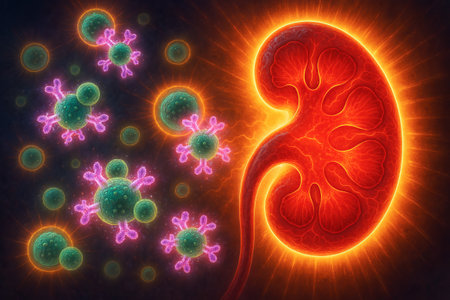

Immune system attacking kidneys with cells illustrating autoimmune disease concept in vivid digital artwork. concept of medical illustration, kidney health, immune response.